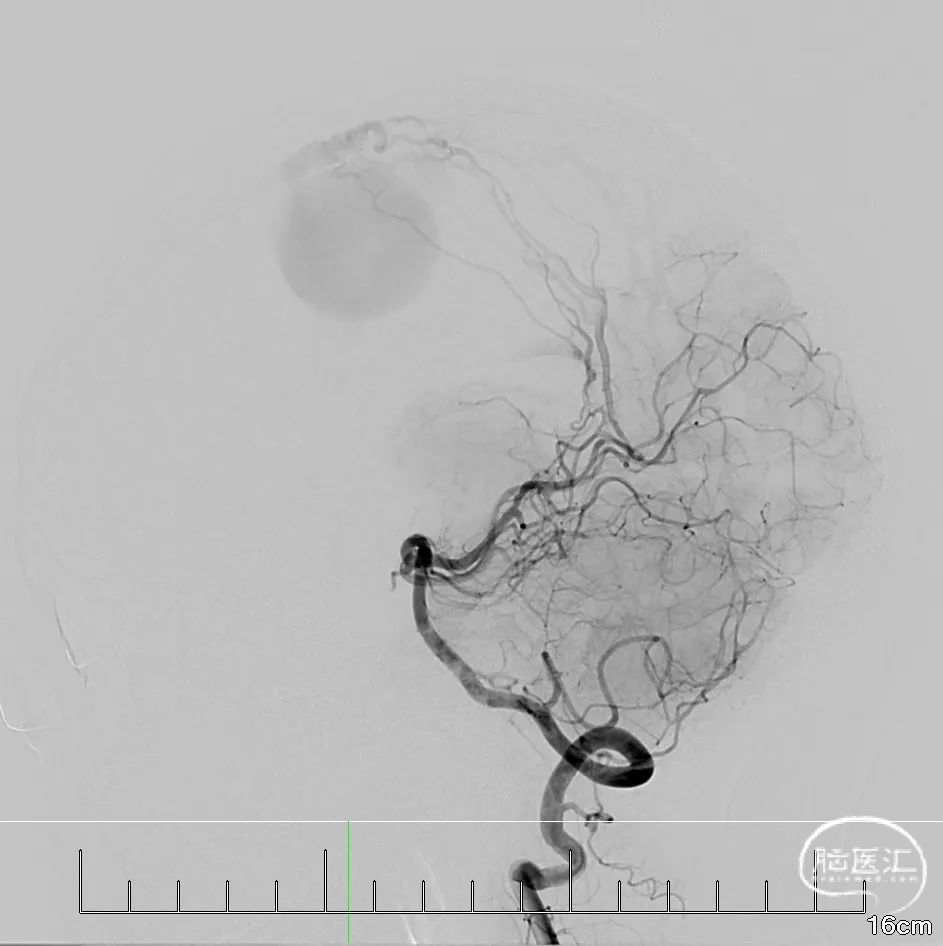

术前影像学资料(DSA)

L-ECA正位

L-ECA侧位,可见脑膜中动脉向瘘口供血,血流向上矢状窦顺行引流